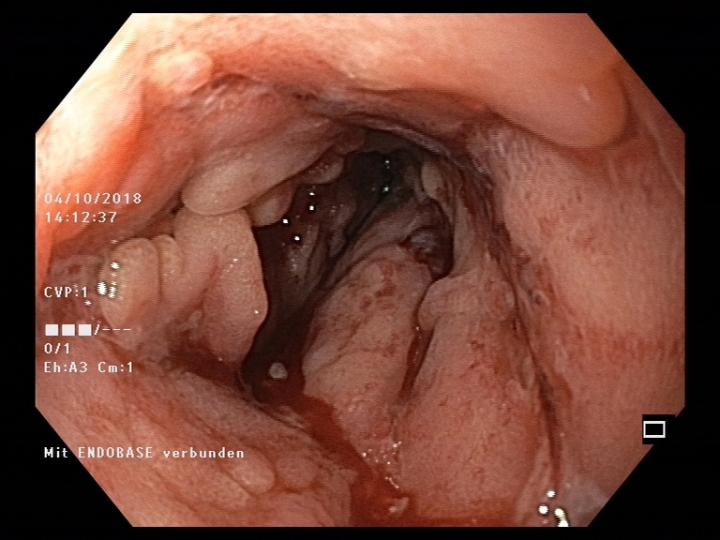

There are different forms of inflammatory bowel disease (IBD) - Crohn's disease (which affects different segments of the entire intestinal tract) and ulcerative colitis (which affects the large intestine). These conditions affect about 30 people per 100,000 of the European and North American populations. Over the last 10 years the incidence of IBD in Switzerland has sharply increased: in 2004 there were about 12,000 patients compared with 20,000 in 2014. Since IBD usually starts before the age of 35, with major ongoing limitations for the quality of life and ability to work, the conditions also have severe social and economic consequences.

New results have now been reported on the relationships of intestinal bacteria in IBD patients by the research team led by Andrew Macpherson, Bahtiyar Yilmaz und Pascal Juillerat in the Department of Biomedical Research in the University of Bern and the University Clinic of Visceral Surgery and Medicine of the Inselspital. They have discovered that changes of particular species of intestinal bacteria lead to severe relapsing disease resistant to therapy and even make the return of the disease more likely in patients whose active segments of Crohn's disease have been surgically removed. The work is being published in the journal Nature Medicine .